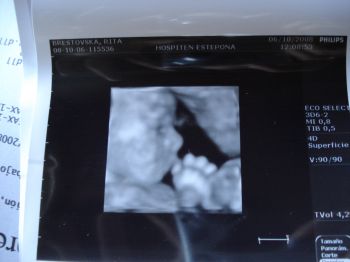

Manó 900 g körül van, és jól éreztem, hogy a bordáimat rugdossa, mert megfordult (eddig mindig faros volt). Dokker szerint már nem valószínű, hogy visszafordulna, mert a feje a legnehezebb, meg így jobban el is fér

Úgyhogy ő is sima szülésre készül, akárcsak én